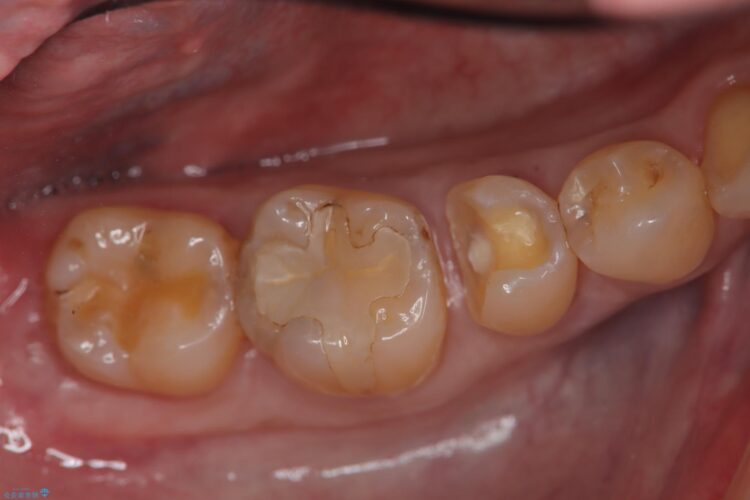

メタルフリーにしたいとご来院された患者様です。

レントゲン検査の結果、古い金属の詰め物の内部に二次的な虫歯が見つかりました。